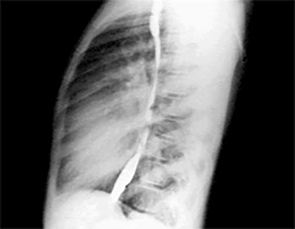

PA and Lateral

Click on the Xrays to enlarge them.

Choose the best interpretation of the chest X rays:

Dilated pulmonary trunk

RV enlargement + dilated

pulmonary trunk +

increased pulmonary vascularity

RV enlargement +

LA enlargement

RV enlargement + small pulmonary trunk +

decreased pulmonary vascularity

Normal